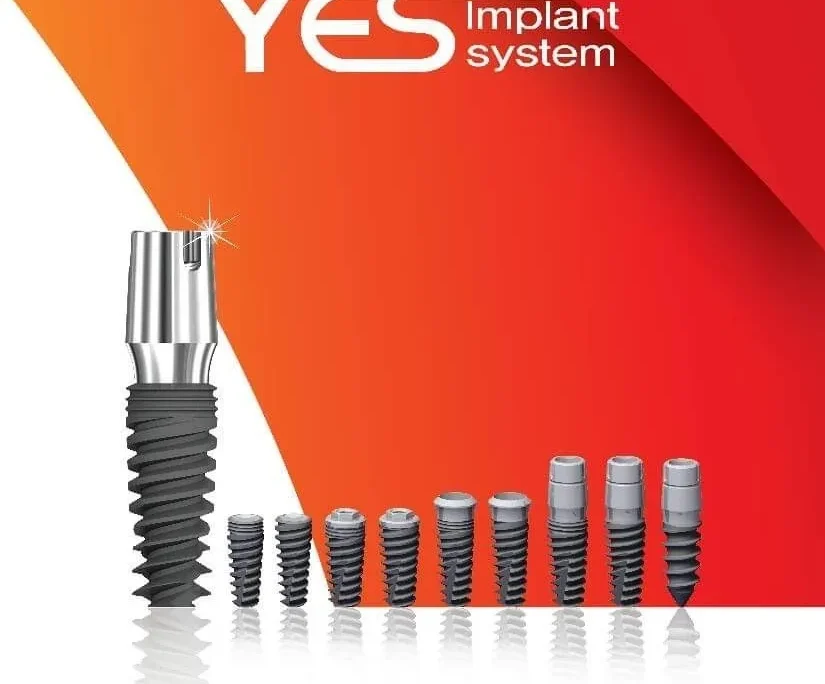

Trồng răng Implant Hàn Quốc là phương pháp phục hình và khôi phục răng hiện đại hiện nay. Phương pháp này thường có chi phí tối ưu